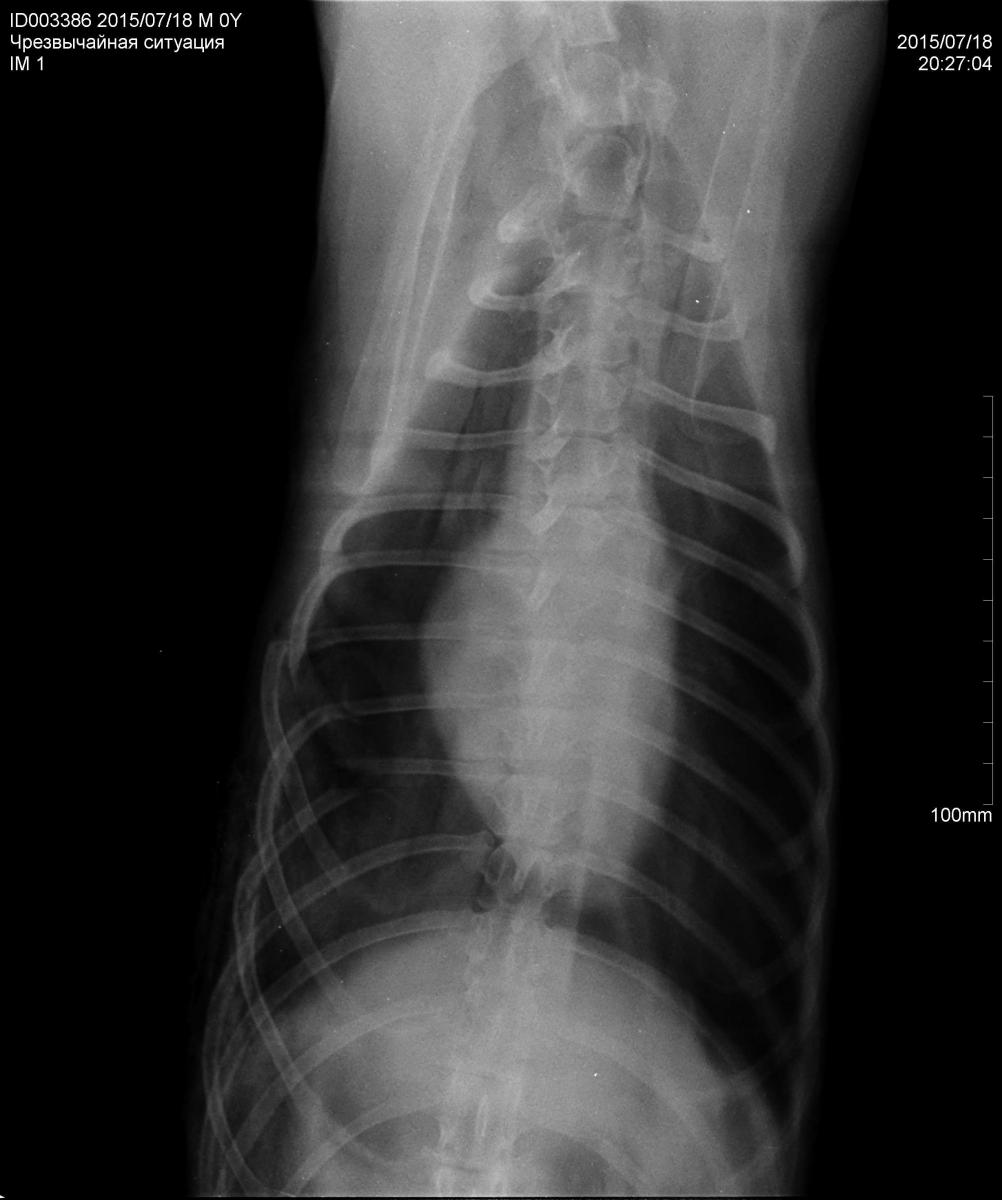

Александр, здравствуйте. Хочу проконсультироваться. У кобелька КФЛ, 3 года, после драки с овчаркой, (а может и хозяин овчарки ногу приложил?), сломаны три ребра, задето легкое. Имел место пневмоторакс. В ветклинике нам сделали рентген (прилагаю), наложили фиксирующую повязку. Рану от прокуса в правом боку обработали. В этой повязке ходим уже 10 дней.

Хирург смотрел нас в субботу. В месте перелома крепитация наличествует. Повязку сказали снимать полностью 10 августа. То есть три недели в ней. А прогноз таков, что одно ребро так и не срастется. Сшивать они их не сшивают. Я спросила, насколько это страшно? Хирург махнул рукой: ерунда. На Ваш взгляд это так и есть? Сможем ли мы бегать подолгу, на охоту его брать? Пес очень подвижный и азартный, на поводке ходить для него мучение. Может стоит настоять на операции? Или можно оставить как есть?

брунова с. армас.jpg

Здравствуйте Марина. А проекция одна? Хотелось бы вторую проекцию. Но и без нее могу сказать, что сломанные ребра дискомфорта вызывать по идее не должны, так как произойдет "омозоливание" они не смогут уже проткнуть легкое или нанести иной вред. Но мы говорим об высоких физических нагрузках, и тут появляется вопрос. Я бы вам рекомендовал с собакой и со снимками но в двух проекциях, показаться к хирургу. Он сможет оценить необходимость (целесообразность) проведения остеосинтеза.

Проекция одна. Вот что сняли, то мне и прислали. Сейчас поеду в другую ветклинику. Вчера заметили, что в районе правой ключицы у него как будто воздух под кожей скопился.

Делайте вторую проекцию. Воздух под кожей, это эмфизема подкожной клетчатки, он еще своеобразно крепитирует? (ну как свежий снег под ногами). В вашем случае видимо в следствии травмы.

Это говорит о проникающем ранении в грудную полость. Нужно делать операцию по закрытии дефекта. Ребра лучше все таки собирать мне так кажется, но как я уже писал, вам лучше к хирургу.

Да, крепитирует. Были у другого врача. Пощупал, сказал то же что и первый, оно само выйдет. Я вот тоже не пойму откуда выйдет? Посмотрел рану, не нашел ничего подозрительного и просто перебинтовал. Сказал, что сделает рентген, когда будеп снимать повязку. Я так понимаю, нам надо наверное хорошую клинику в Москве искать?

Воздух выйдет, это не страшно. Страшно если отверстие есть и он туда постоянно поставляется, идет системное нарушение, сердце более усиленно "качает" кровь, легкие тоже работают усиленно. Все зависит от того сколько того самого воздуха, каков размер отверстия. Может там и правда ничего страшного, мне от сюда из Питера плохо видно ). Хотя бы проекцию вторую увидеть, а они что то вредничают... Думаю все таки поищите клинику с хирургами, рентгеном. Странно что вам откладывают рентген и так далее, это же все таки деньги (простите за прямолинейность) Может там действительно все не так страшно и вас не хотят обременять финансами. Честно говоря для меня загадка. Я за то, что бы исследования были качественными в должном размере. Поспрашивайте ребят из Москвы, кто где лечится, может знают хорошую клинику.